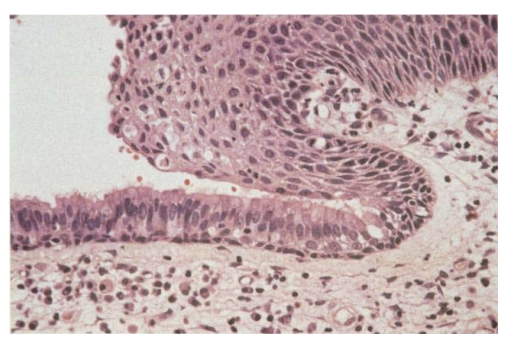

57-årig mand henvist fra e.l. til gastroskopisk udredning grundet længerevarende anamnese med daglige refluxsymptomer (halsbrand, sure opstød og sviende smerter i epigastriet). Ved gastroskopi ses i distale esophagus uregelmæssige røde tunger der strækker sig op i esophagus. Der biopteres herfra og mikroskopisk ses forandringer, som på billedet. Hvilke epitelforandringer ses i biopsien?

a. Metaplastisk cylinderepitel af intestinal type

b. Dysplasi af let grad

c. Alderbetinget atrofi

d. Karcinom

e. Hyperplasi

*a. Metaplastisk cylinderepitel af intestinal type

Det normale pladeepithel i oesophagus er erstattet af cylinderepithel: Barrets oesophagus